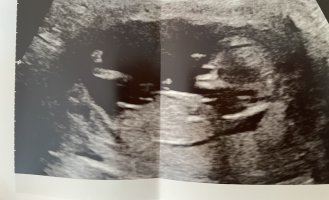

Ei näy nubia. Vain napanuoran alkupää näyttäisi olevan toi pätkä tossaHaluaako joku yrittää analysoida meidän bebeä? Ultran aikaan viikkoja on ollut 12+6.

Oon yrittänyt lukea nubista ja katsella erilaisia kuvia mut en nyt edelleenkään tiedä mitä kohtaa tässä pitäisi tuijotellaoltiin analysoivinamme kovastikin häntä pojaksi ultrassa mutta myöhemmin kotona tajusin, että ollaan varmaan katteltu napanuoraa koko ajan…